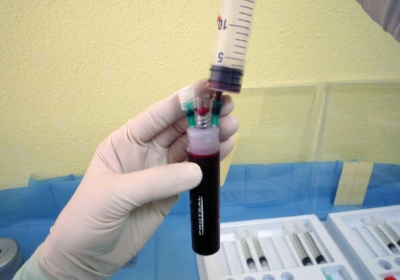

FACTORES DE CRECIMIENTO Y PLASMA RICO EN PLAQUETAS (PRP)

En España la aplicación del PRP es un medicamento de uso humano. Así lo determinó la Agencia Española de Medicamentos y Productos Sanitarios del Ministerio de Sanidad, Servicios Sociales e Igualdad” en la Resolución del 23 de mayo de 2013. Allí se resuelve “Clasificar el uso terapéutico no sustitutivo del plasma autólogo y sus fracciones, componentes o derivados como medicamento de uso humano para atender necesidades especiales.

”La obtención y preparación del PRP deben hacerla profesionales debidamente formados, utilizando equipos homologados y teniendo las autorizaciones legales correspondientes. Por ejemplo, pipear en sistema abierto, es decir, contaminado, y sin cámara de flujo laminar se corre el alto riesgo de producir sepsis al infiltrar una articulación cerrada, que hace las veces de una incubadora.

Existen muchos GF y se encuentran en diversos lugares donde exista tejido conectivo como el hígado, torrente circulatorio, otras células…aunque es en los granulos alfa de las plaquetas su hubicación principal.(9,13,43). Se destacan algunos como: